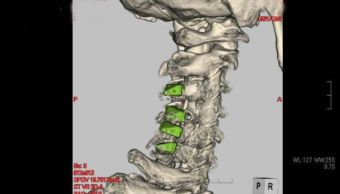

05 頚椎後縦靭帯骨化症 椎弓形成術

頚椎後縦靭帯骨化症(けいつい こうじゅうじんたいこっかしょう)とは?

頚椎をつなぐ靭帯が骨のように固くなり、さらに厚くなって脊髄を圧迫する病気です。

手足のしびれや筋力の低下をきたすことがあります。

椎弓形成術

脊髄(神経の束)が通るトンネルを、屋根を上げるような形で広くする手術です。

OPLL 術前

OPLL 術後